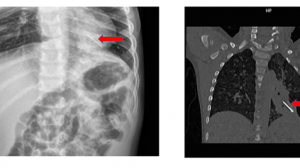

Lúc 16 giờ 08/05/2021, bệnh viện Nhi đồng Thành phố tiếp nhận một trường hợp trẻ Tr. K. Ng 3 tuổi, nữ, ngụ ở Long An, nhập viện trong tình trạng đau bụng, nôn ói nhiều. Bệnh sử ghi nhận cách nhập viện 2 ngày, trẻ đau bụng, kèm ói 5-6 lần, không đi tiêu, được khám bác sĩ tư, chẩn đoán rối loạn tiêu hóa, điều trị men tiêu hóa, thuốc chống nôn, tình trạng không cải thiện, trẻ đau bụng nhiều, ói nhiều ra dịch xanh nên nhập viện Nhi đồng Thành phố. Tại đây trẻ được các bác sĩ thăm khám, xét nghiệm, chẩn đoán hình ảnh Xquang bụng đứng không sữa soạn cho thấy có hình ảnh mực nước hơi kèm dị vật kim loại theo dõi pin hoặc nam châm, nên được hội chẩn bác sĩ ngoại khoa chuyển phòng mổ tiến hành phẫu thuật nội soi ghi nhận các quai hỗng tràng dãn, thành dày. Tại hố chậu phải có một vài quai ruột tím bầm. Gỡ dính, bộc lộ vị trí tắc thấy có 2 viên bi nam châm đường kinh # 1cm, từ hai quai ruột khác nhau đang hút vào nhau gây thủng ruột tại vị trí tiếp xúc. Mở rộng trocar rốn. Đưa 2 quai ruột chứa hai viên nam châm ra ngoài, lấy dị vật, thành ruột phù nề, xuất huyết, tím nhạt, cho ruột vào lại ổ bụng. Nội soi kiểm tra từ gốc hồi manh tràng: vị trí thủng thứ nhất cách van hồi manh tràng 30cm và vị trí thủng thứ 2 cách van hồi manh tràng 100cm xén chỗ hoại tử và khâu vá 2 lỗ thủng 2 lớp. Sau mỗ hiện tại trẻ tỉnh, môi hồng/khí trời, không sốt, sinh hiệu tạm ổn, bụng mềm không chướng, được điềua trị dịch truyền dinh dưỡng, kháng sinh, giảm đau. Được biết trẻ được ông ngoại nuôi giữ trẻ vì ba mẹ đi làm hàng ngày, trẻ chơi với búp bê điện tử, bên trong có các viên bi nam châm, nên trẻ tháo lấy ra nuốt vào đường tiêu hóa mà gia đình không hay biết.